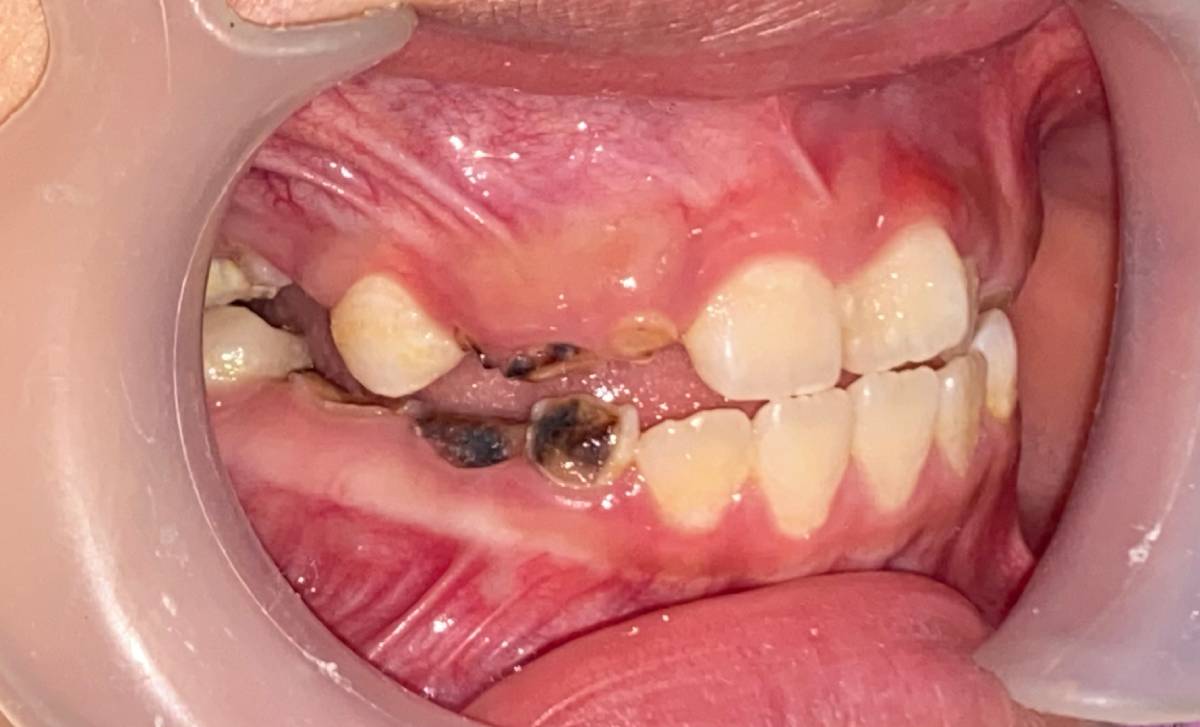

Tác hại của đường và axit đối với răng

Đường là nguyên nhân hàng đầu gây sâu răng ở trẻ em. Khi trẻ ăn quá nhiều bánh kẹo, socola, nước ngọt hoặc đồ uống có gas, lượng đường trong khoang miệng tăng cao. Vi khuẩn sẽ chuyển hóa đường thành axit, làm mòn men răng và hình thành lỗ sâu.

Bên cạnh đó, đồ uống có gas chứa axit mạnh, có thể làm bào mòn men răng, khiến răng yếu và dễ gãy.

Vệ sinh răng miệng là thói quen bắt buộc để giữ răng khỏe mạnh. Nếu trẻ lười đánh răng hoặc đánh răng sai cách, mảng bám sẽ tích tụ, dẫn đến:

-

Sâu răng và viêm nướu.